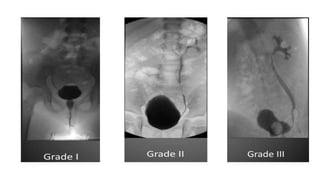

 vesico-ureteral reflux

3. Vesico ureteric reflux.